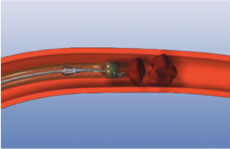

脳梗塞急性期の治療法として組織型プラスミノゲン・アクティベータ(t-PA:一般名アルテプラーゼ)静注による血栓溶解療法が2005年に認められてから、早くも13年近くが経過し、2012年9月からはt-PA静注療法の対象患者が発症後3時間から4.5時間に延長されました。2010年10月から発症後原則8時間以内の主幹動脈閉塞に対し、Merciリトリーバルシステムを用いた血栓除去による血管内治療が認められました。2011年から血栓除去用カテーテルであるPenumbra systemが保険承認されました。これは血栓の直前まで吸引用カテーテルを持っていき、そこから持続的に吸引を行い、血流を再開通するものです。(図1-a、b)2014年7月からステント型血栓回収機器(図2)が導入されました。ステント型血栓回収機器は、ステントを閉塞血栓部位に留置することで血栓がステント内に捕捉され、その機器を回収することで血栓を除去し、再開通を目指すものです。現在は3種類の血栓除去用ステントの使用が可能です。(図3)2015年にナッシュビルで開催された国際脳卒中カンファレンスでは脳主幹動脈閉塞に対して、ステントを用いた血栓除去術が保存的治療と比較して有意に予後良好であることが示されました。現在、ステントを用いた血栓除去術は欧米、本邦で必須の治療となっており、当院においても、飛躍的に再開通率が上がり、TICI2b以上の再開通を全症例の約95%で得られております。

| 図2:ステント型血栓除去デバイスビデオ |

![]() 図3:ステント型血栓除去デバイス |